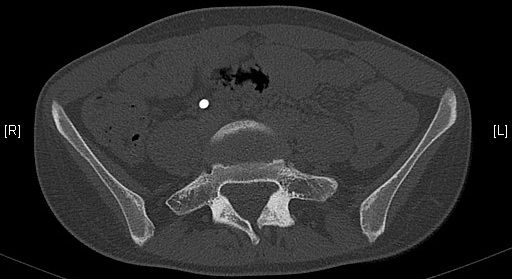

Néo-articulation transverso-sacrée droite